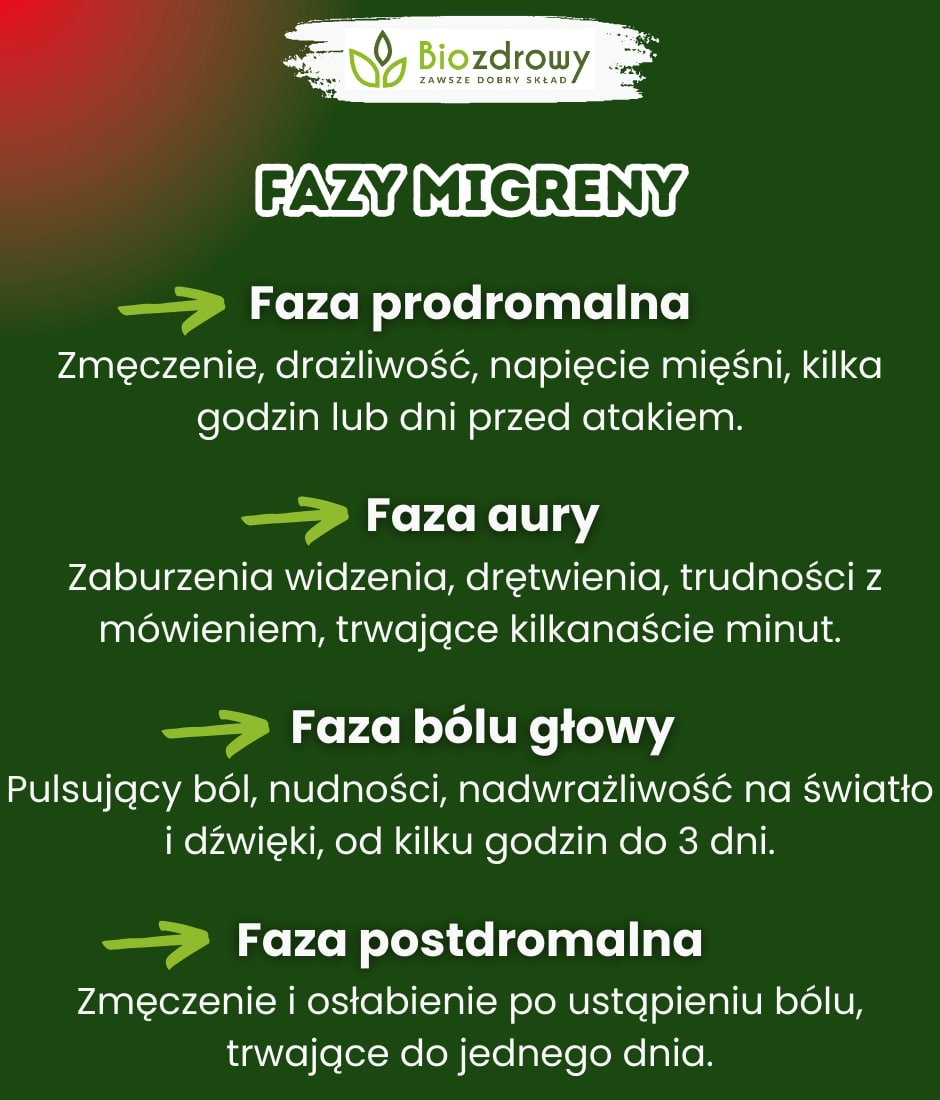

Migrena często przebiega w kilku charakterystycznych fazach, które następują po sobie od momentu pojawienia się pierwszych sygnałów aż do zakończenia napadu. Każda z tych faz może objawiać się innymi symptomami i wymagać odmiennego podejścia, aby złagodzić dolegliwości.

- Faza prodromalna (objawy zwiastujące). Faza prodromalna, zwana także fazą zwiastunową, występuje u wielu osób na kilka godzin, a czasem nawet dni przed bólem głowy. Objawy zwiastujące mogą obejmować zmęczenie, drażliwość, wzmożone pragnienie, częste ziewanie oraz napięcie mięśni. W tej fazie organizm sygnalizuje, że zbliża się napad migreny.

- Faza aury. Aura to specyficzny zespół objawów neurologicznych, który pojawia się tuż przed bólem głowy. Aura migrenowa trwa zazwyczaj od kilku do kilkudziesięciu minut i może obejmować zaburzenia widzenia, takie jak błyski światła, zygzakowate linie, mroczki przed oczami, a także drętwienia lub mrowienia, zwykle w dłoniach, ramionach lub twarzy. U niektórych osób pojawiają się także trudności z mówieniem.

- Faza bólu głowy (ataku). Faza bólu głowy to najbardziej intensywna część napadu migreny. Ból jest zazwyczaj jednostronny, pulsujący i może nasilać się przy aktywności fizycznej. Objawom bólowym często towarzyszą nudności, wymioty oraz nadwrażliwość na światło, dźwięki i zapachy. Faza bólu może trwać od kilku godzin do nawet 3 dni.

- Faza postdromalna (faza ponapadowa). Po ustąpieniu bólu głowy następuje faza postdromalna, zwana także fazą ponapadową. W tym czasie organizm powraca do normalnego stanu, co może trwać od kilku godzin do jednego dnia. Często pojawia się uczucie zmęczenia, osłabienia, obniżonej koncentracji i drażliwości. Niektórzy opisują to jako „kaca migrenowego”.